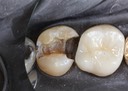

Larry Fujioka #30 pre-op